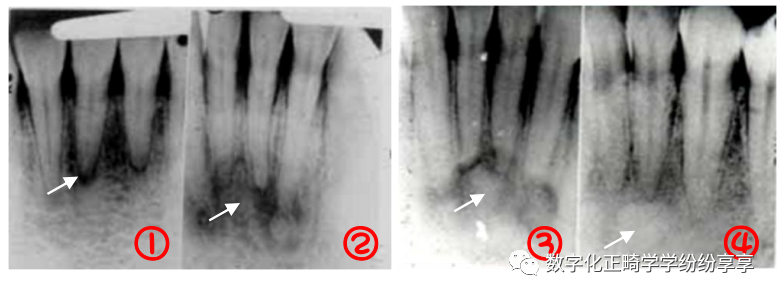

牙发育异常 Dental anomalies:

畸形中央尖 曲面断层片怎么看正畸【曲面断层片(全景片)】如何解读和查看:牙周?牙体?牙髓?关节?_https://www.jmylbn.com_新闻资讯_第16张

牙内陷

曲面断层片怎么看正畸【曲面断层片(全景片)】如何解读和查看:牙周?牙体?牙髓?关节?_https://www.jmylbn.com_新闻资讯_第17张

①右上 2 畸形舌侧尖(伴阻生牙);②左上 2 畸形舌侧窝;③右上 2 牙中牙

融合牙

曲面断层片怎么看正畸【曲面断层片(全景片)】如何解读和查看:牙周?牙体?牙髓?关节?_https://www.jmylbn.com_新闻资讯_第18张

分别为右下 1、2 的完全性融合和不完全性(牙冠)融合